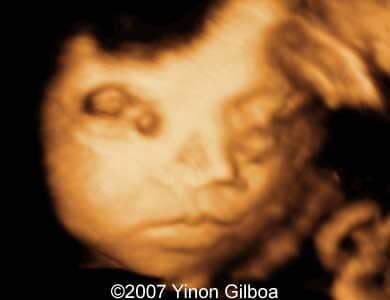

These are some ultrasound images obtained at 30th week of pregnancy. Previous ultrasonography scans at 15th and 24th week were normal. Our investigation revealed bilateral dacryocystocele of the fetus. No other anomalies were found.

Images 2 and 3: 3D images showing small prominences of the medial canthi representing bilateral dacryocystocele.